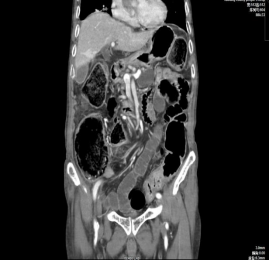

近期,已经三天没有排气排便的张爷爷腹痛难忍,终于熬不下去,在家人的带领下来到浙大二院台江分院就诊。急诊CT平扫提示结肠广泛扩张,明显的肠梗阻征象,被安排到外一科住院治疗,给予禁食、插胃管和补液等支持治疗,症状有所缓解。

住院后进一步的增强CT检查显示:直肠上段有个明显的肿瘤,找到了导致肠梗阻的元凶。经过保守治疗,张爷爷的梗阻症状并未减轻且有加重倾向,管床医师建议行外科手术切除肿瘤并解除梗阻,但家属顾及高龄和手术风险,难以决定手术治疗,只能继续保守治疗。但随着时间推移,患者病情仍持续加重,张爷爷肚大如鼓,如果不进行手术,恐怕只能止步于97岁。